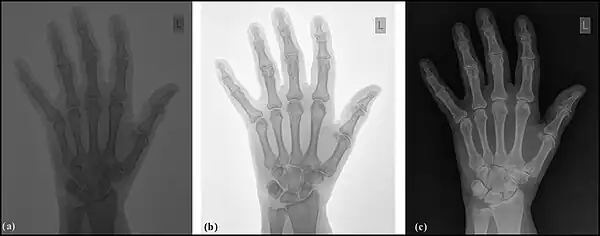

Image sampling is the process used to digitise the spatial information in an image. It is typically achieved by dividing an image into a square or rectangular array of sampling points - see the following figure. Each of the sampling points is referred to as a picture element - or pixel to use computer jargon. Although in the context of DR image receptors, the term detector element, or del, is also used. Naturally, the larger the number of pixels or dels, the closer the spatial resolution of the digitised image approximates that of the radiation pattern transmitted through the patient – see the following figure, panels (a) and (b).

Note that each pixel represents not a point in the image but rather an element of a discrete matrix. Distance along the horizontal and vertical axes is no longer continuous, but instead proceeds in discrete steps, each given by the pixel size. With larger pixels, not only is the spatial resolution poor, since there is no detail displayed within a pixel, but grey-level discontinuities also appear at the pixel boundaries (pixelation) - see panel (b) in the figure. The spatial resolution improves with smaller pixels and a perceived lack of pixelation gives the impression of a spatially continuous image to the viewer.

Image quantisation is the process used to digitise the brightness information in an image. It is typically achieved by representing the brightness of a pixel by an integer whose value is proportional to the brightness. This integer is referred to as a 'pixel value' and the range of possible pixel values which a system can handle is referred to as the grey scale. Naturally, the greater the grey scale, the closer the brightness information in the digitised image approximates that of the original image – see the following figure, panels (a) and (c). The process can be considered as the digitisation of image brightness into G shades of grey. The value of G is dependent on the binary nature of the information coding. Thus G is generally an integer power of 2, i.e. G=2m, where m is an integer which specifies the number of bits required for storage. Examples of values of G are 1,024 (m=10) in fluoroscopy, 2,048 (m=11) in angiography and 4,096 (m=12) in digital radiography. Note that the slight difference between the brightness in an analogue image and its pixel value in the digital image is referred to as the quantisation error, and is lower at larger values of G.

- Contrast enhancement can also be effected through manipulation of the image's statistical histogram and is illustrated in Figure 5.8. A histogram is a plot of the frequency of occurrence of each pixel value in an image - see panel (a) for an example, where this frequency is plotted as a function of pixel value. It can be seen that pixels from the black surroundings of the hand are indicated by the peak at low pixel values. It can also be seen that the pixel values representing bone and tissue attenuation form a broad range of lower frequencies extending to just over half the grey scale. Indeed the pixels of the 'L' marker can be seen to form an isolated blip at a pixel value of 75. Note that the term frequency as used here should not be confused with the term spatial frequency we have been using in our discussion of Fourier techniques.